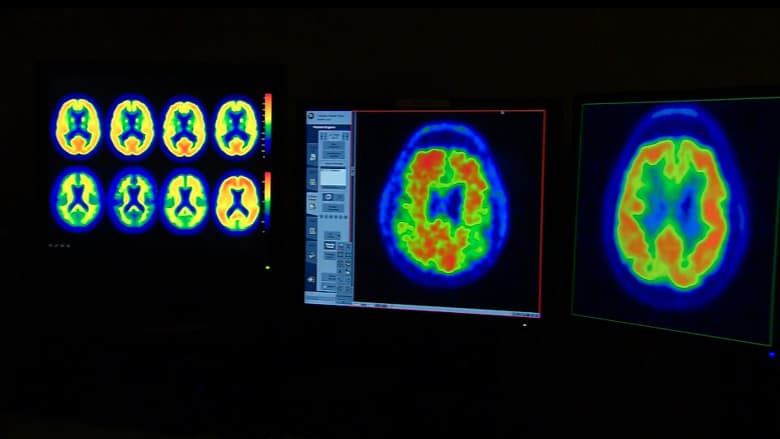

إرشادات جديدة لعلاج إصابات الدماغ.. إليك ما ينبغي معرفته

تُعدّ إصابات الدماغ الرضّية سببًا رئيسيًا للوفاة والإعاقة في الولايات المتحدة. وهي أكثر شيوعًا ممّا تتصوّر، إذ تُصيب ملايين الأمريكيين سنويًا. كانت إصابات الدماغ الشديدة تُعتبر في السابق بمثابة حكم بالإعدام، لكن لأول مرة منذ عقود، قد يُغيّر معيار جديد للرعاية الصحية هذا الواقع.